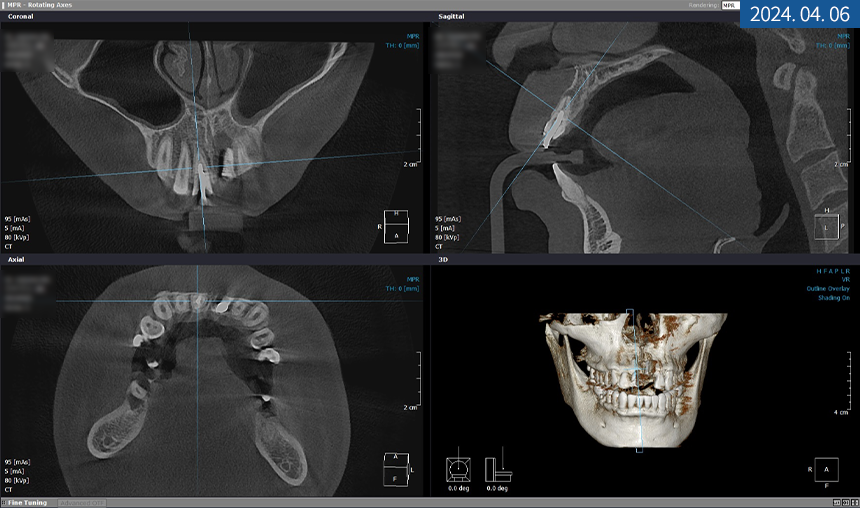

20대 남성분의 X-ray 사진

X-ray 상 앞니 손상과 치근 염증이

심하다는 결과를 봐서는 발치가 필요해 보였으며

좌측 하악 어금니도 뿌리 밑에 염증이 생겨

치아 보존이 힘든 상황이었습니다.

먼저 상악 #21번 어금니 발치를 진행하기로 했고

발치 후 기존 영구치 방향을 따라

인공 치근을 심은 후

필요시 GBR 골 이식재를 넣고

차폐막으로 덮기로 했습니다.

골 유착이 되는 동안에는

좌측 하악 어금니에 픽스처를 식립하고

전체 치주 질환을 개선하면서

경과를 관찰하기로 했습니다.